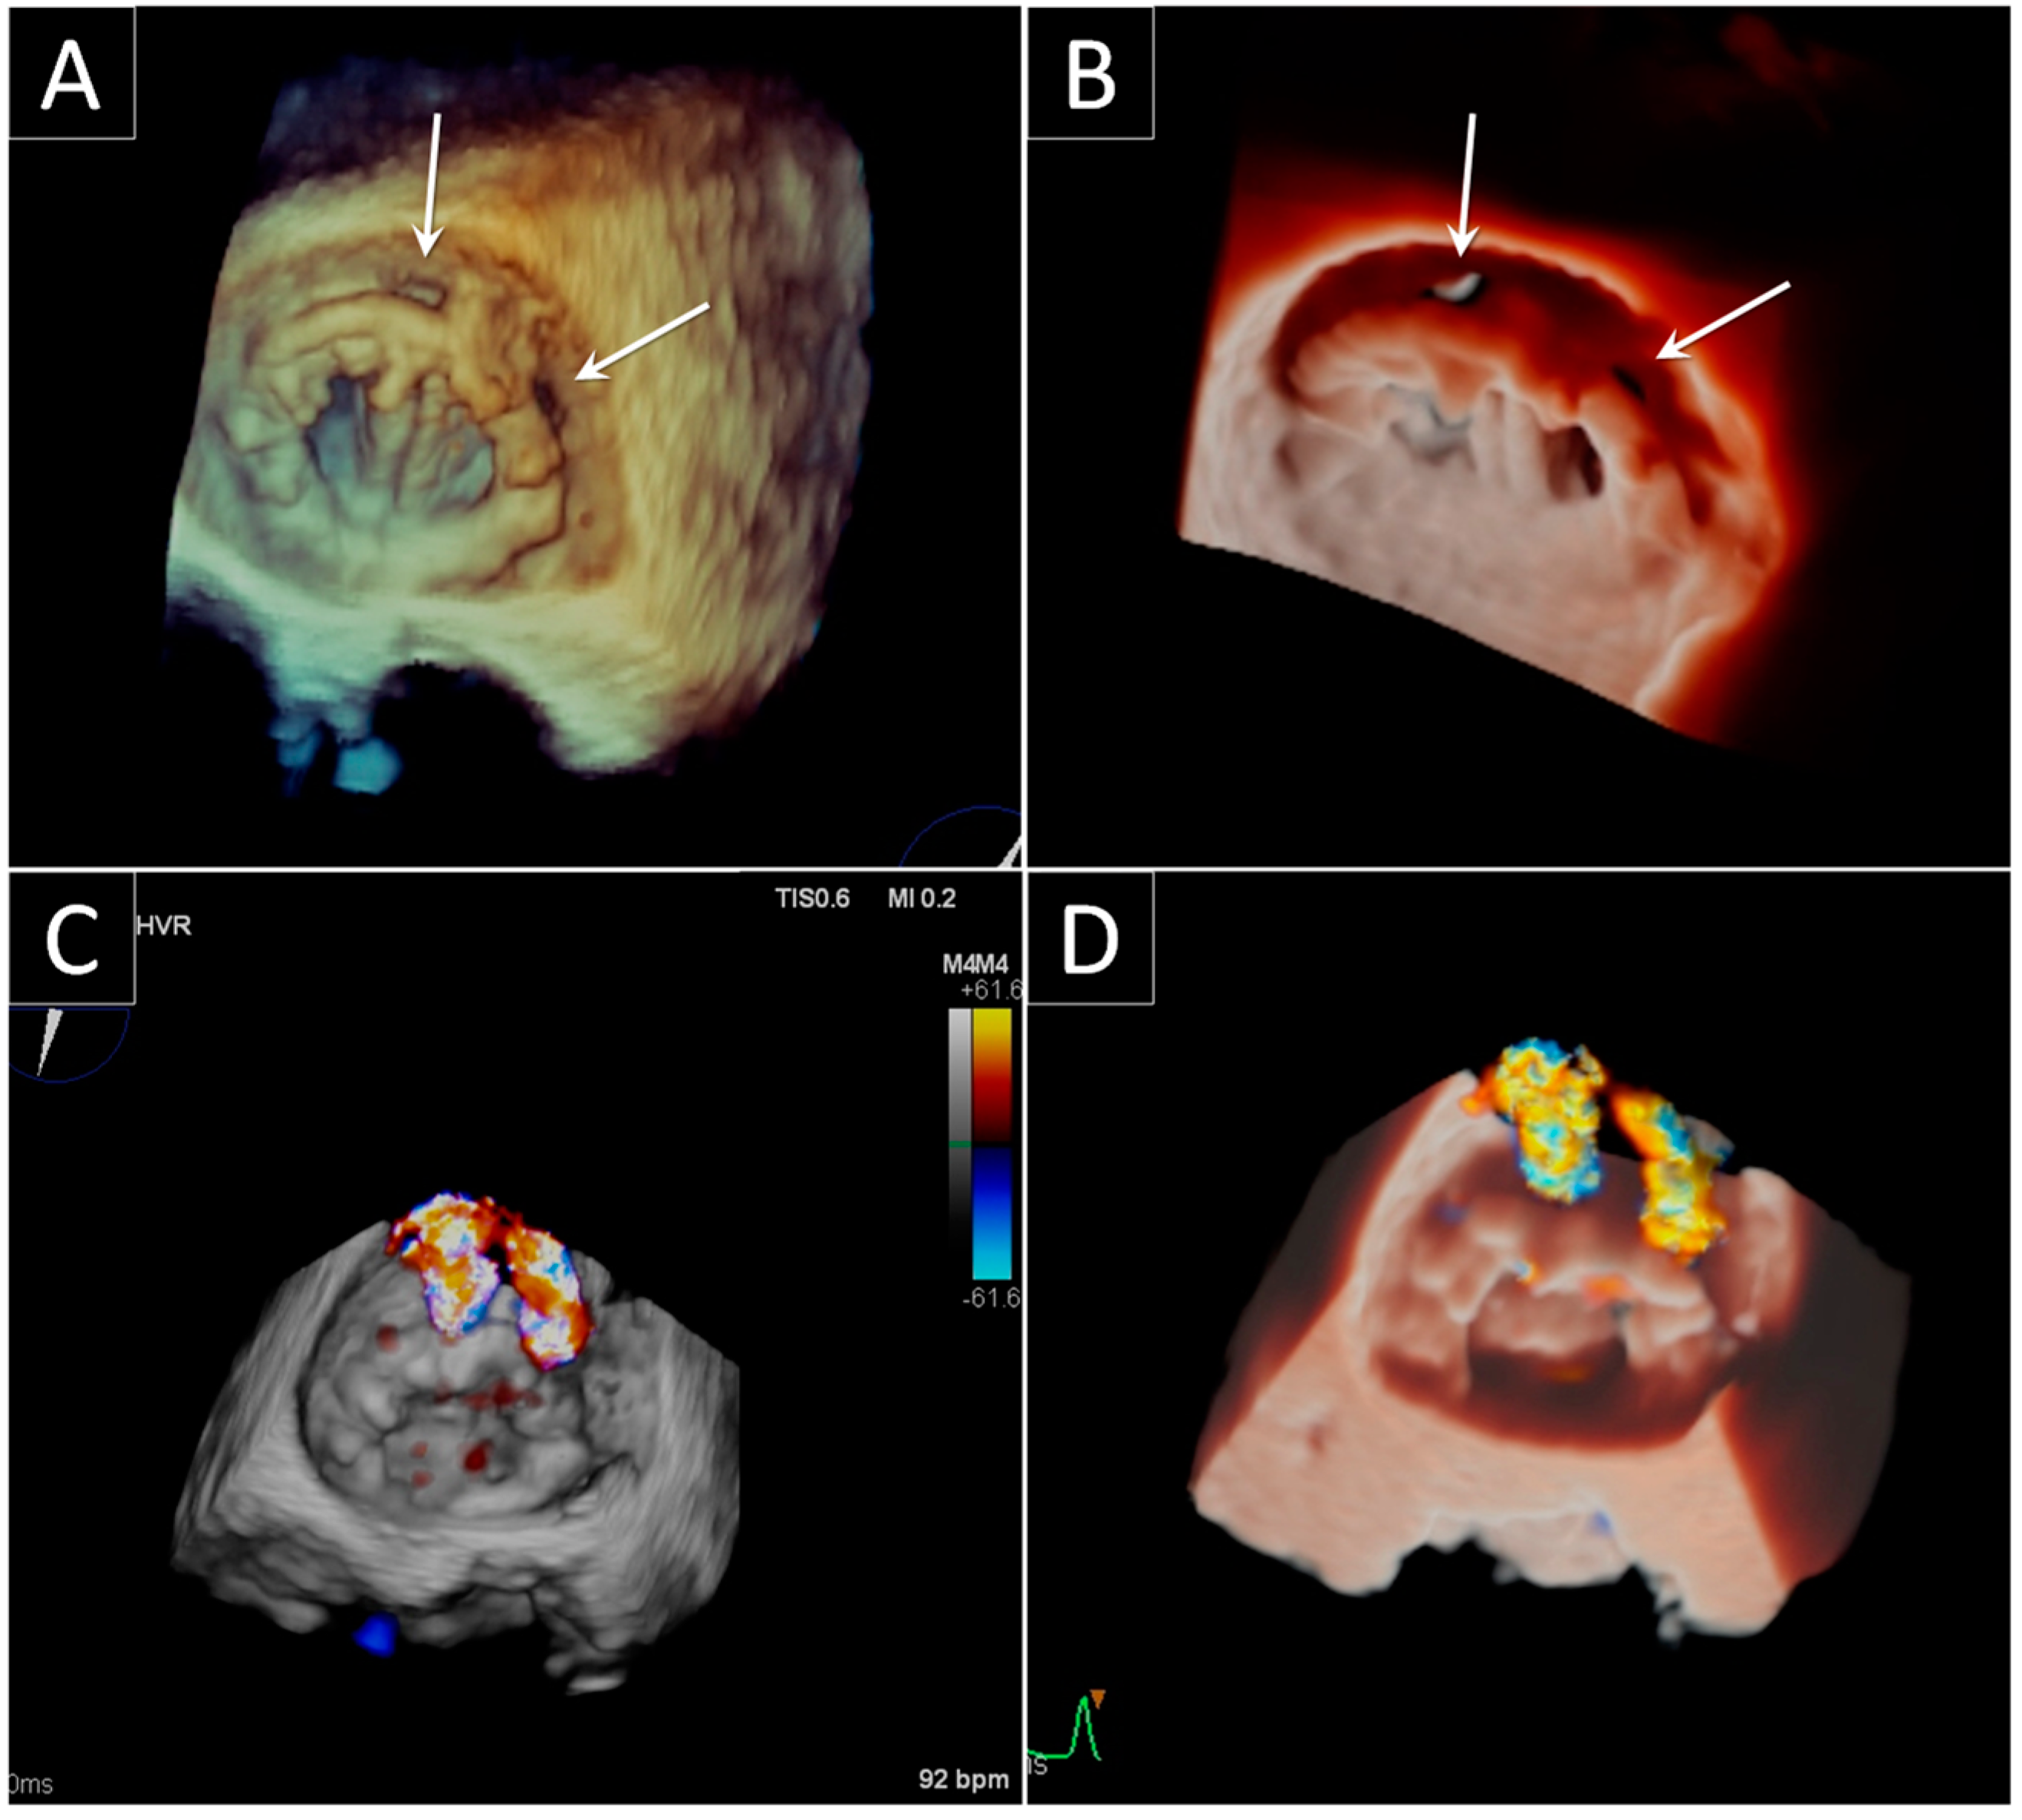

3. Prosthetic Paravalvular Leak

3.1. Mitral Paravalvular Leak